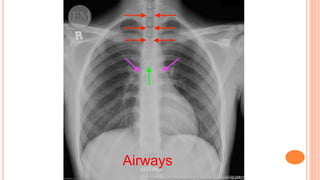

•Airways

A Airways

The trachea should be central or slightly to the right. If it is deviated, check whether it is due

to the patient's position or another pathological cause.

Airways